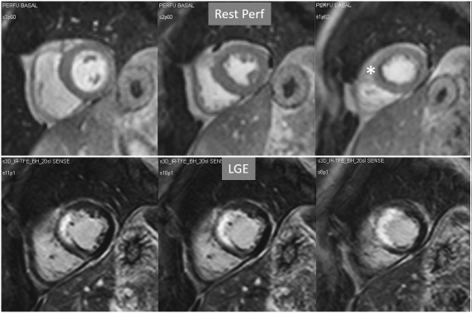

Particularly important, in practice, is the issue of perfusion studies in patients with previous MI. In theory, a basal rest perfusion study should exhibit a reduced signal intensity in the infarcted area, as is the case in the acute phase of a large transmural MI (Fig. 14A). However, not infrequently, the presence and extent of a rest perfusion defect does no correlate with the actual area of necrosis in either, acute (Fig. 14B) or chronic MI (Fig. 15). Signal intensity in areas of previous MI is thus, not dependent merely on the presence of scar tissue, but some other factors lead to differences in CA concentration between MI and remote regions and, in this sense, rest perfusion CMR cannot be equated to SPECT studies, where rest defects are directly related to the presence of infarcted myocardial tissue not amenable to radiotracer uptake [45].

Fig. 14.Rest perfusion after acute myocardial infarction. (A) Frames from different sequences in a case of acute MI showing, from left to right, (1) gross transmural defect at the rest perfusion study (arrow); (2) signs of regional myocardial edema at STIR T2, with a mid-line low intensity region which proves to be due to (3) intramural hematoma at T2* sequence; (4) persistence of hypoperfusion at Early Gadolinium Enhancement (EGE); and (5) transmural anteroseptal necrosis with a subendocardial area of microvascular obstruction (arrow). (B) The same series of sequences in another patient with AMI showing (1) mild subendocardial defect at rest (arrow); (2) regional edema; (3) absence of hematoma at T2*; (4) lack of persistent defect at EGE; and, finally, (5) a transmural infero-lateral LGE (arrow) without microvascular obstruction.

Fig. 15.Rest perfusion in chronic myocardial infarction. Basal rest perfusion study showing a reduced subendocardial septal defect (asterisk) at the apical septum in a patient with an extensive old anteroseptal MI evidenced at LGE.